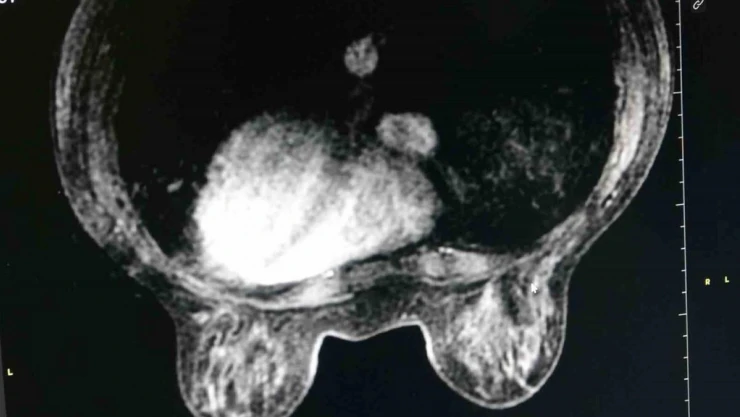

Dünyada, önemli bir halk sağlığı sorunu olan meme kanseri, kadınlarda en sık rastlanan kanser türü arasında ilk sırada yerini alıyor. Diyarbakır Gazi Yaşargil Eğitim Araştırma Hastanesinde Meme Radyolojisi Uzmanı Dr. Derya Deniz Altıntaş, hastanedeki tanısal meme biriminde özellikle meme kanserinde erken tanının mamografide izlenen mikrokalsifikasyonlar ile konulduğunu belirtti. Altıntaş, “Hastanemizdeki tanısal meme biriminde özellikle memesinde şüpheli bulunan hastaları memesinde şüphe olan hasta grubunu kabul ediyoruz. Bu süreçte hastaların tanı, tedavi yönetimi ve takip kısmını birkaç birimin işbirliği içerisinde olduğu multidisipliner yaklaşımla yapmayı planlıyoruz. Birimimiz özellikle meme kanserinde erken tanıda çok önemli olan mamografide gördüğümüz mikrokalsifikasyonlara yönelik mamografi eşliğinde telle işaretlemenin yapılan bölgede tek hizmet veren birim olma özelliğine sahiptir. Bununla birlikte özellikle hastaların tanı tedavi ve takip süreci bizim için çok önemlidir. Hasta şüphe halinde ve çözüm aşamasında nereye gideceğini bilsin istiyoruz. Tedavi sürecinde güvenli bir şekilde tedavisinin tüm süreçlerini bilsin istiyoruz. Dolayısıyla bir hasta şüpheli bir durum varlığında hiç çekinmeden birimimize başvurabilirler” dedi.